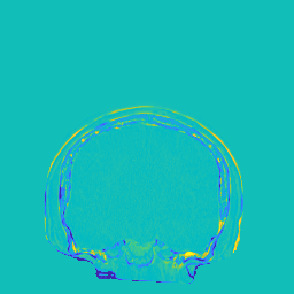

Model-based treatment planning for transcranial ultrasound therapy typically involves mapping the acoustic properties of the skull from an x-ray computed tomography (CT) image of the head. Here, three methods for generating pseudo-CT images from magnetic resonance (MR) images were compared as an alternative to CT. A convolutional neural network (U-Net) was trained on paired MR-CT images to generate pseudo-CT images from either T1-weighted or zero-echo time (ZTE) MR images (denoted tCT and zCT, respectively). A direct mapping from ZTE to pseudo-CT was also implemented (denoted cCT). When comparing the pseudo-CT and ground truth CT images for the test set, the mean absolute error was 133, 83, and 145 Hounsfield units (HU) across the whole head, and 398, 222, and 336 HU within the skull for the tCT, zCT, and cCT images, respectively. Ultrasound simulations were also performed using the generated pseudo-CT images and compared to simulations based on CT. An annular array transducer was used targeting the visual or motor cortex. The mean differences in the simulated focal pressure, focal position, and focal volume were 9.9%, 1.5 mm, and 15.1% for simulations based on the tCT images, 5.7%, 0.6 mm, and 5.7% for the zCT, and 6.7%, 0.9 mm, and 12.1% for the cCT. The improved results for images mapped from ZTE highlight the advantage of using imaging sequences which improve contrast of the skull bone. Overall, these results demonstrate that acoustic simulations based on MR images can give comparable accuracy to those based on CT.